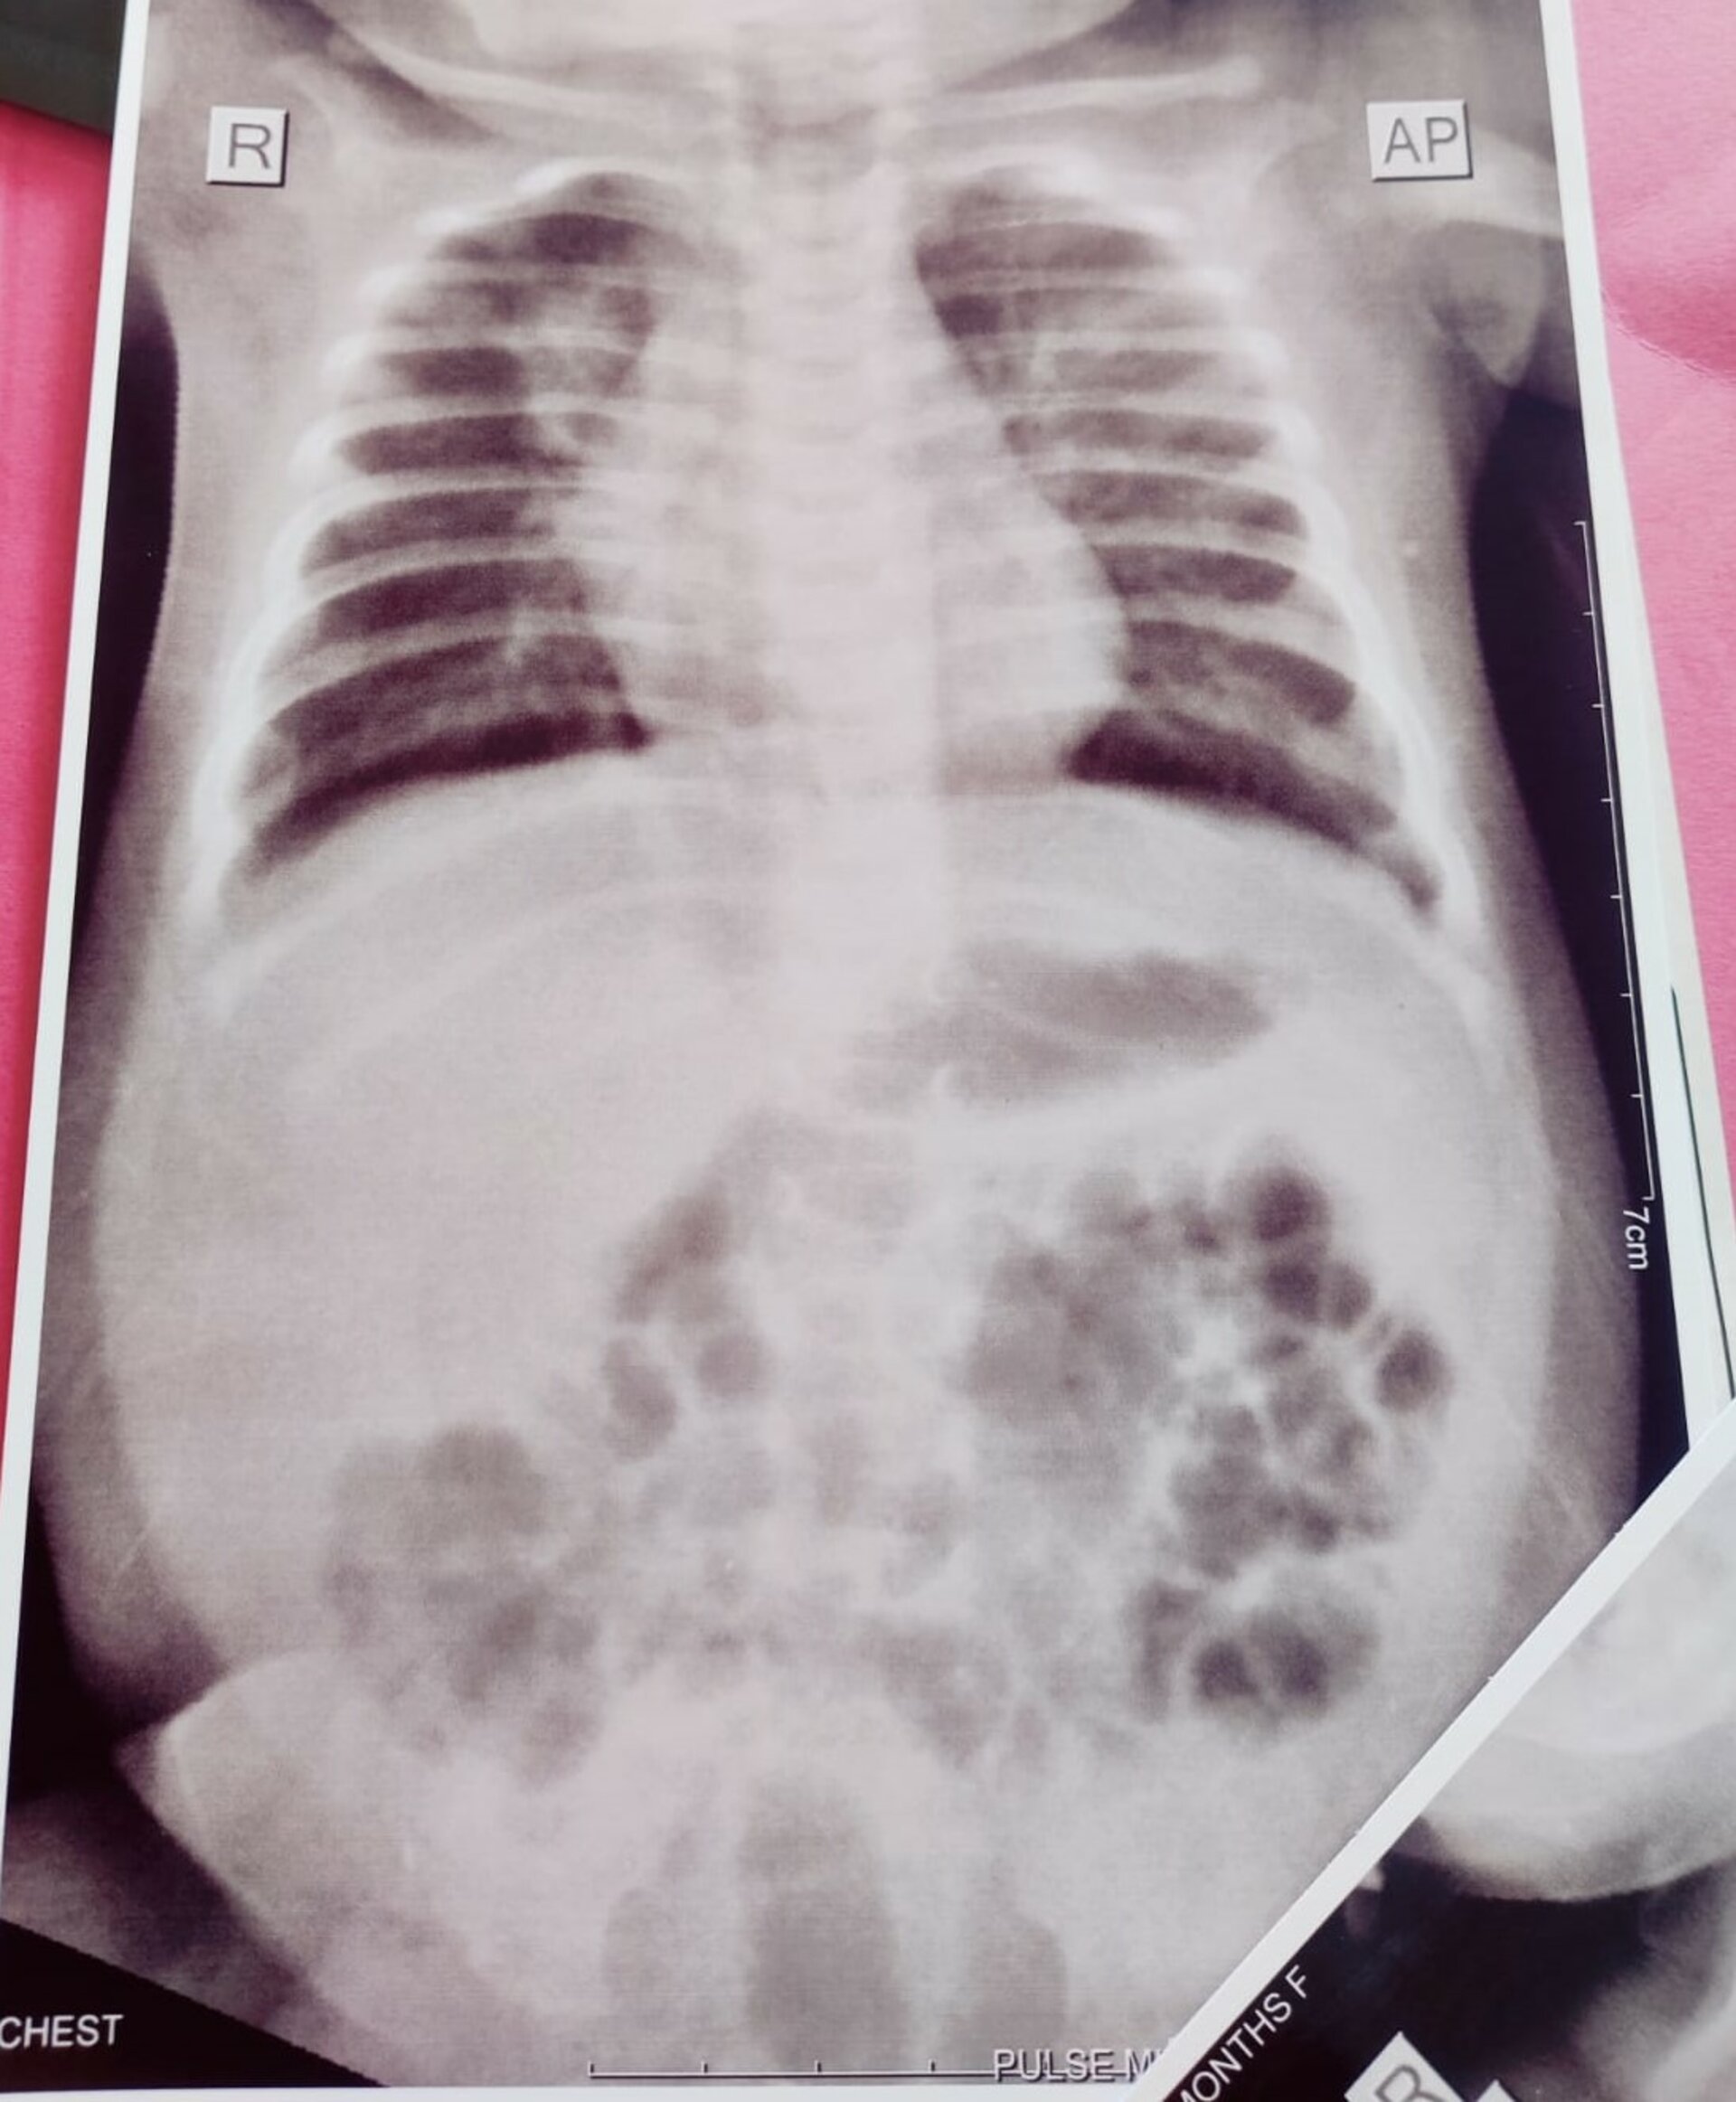

Pulse Hospital Successfully Completes 7th Pediatric Foreign Body Removal Case

In a remarkable feat, the team at Pulse Multi-Speciality Hospital successfully removed a lithium battery from the stomach of a 3-year-old child. Lithi...